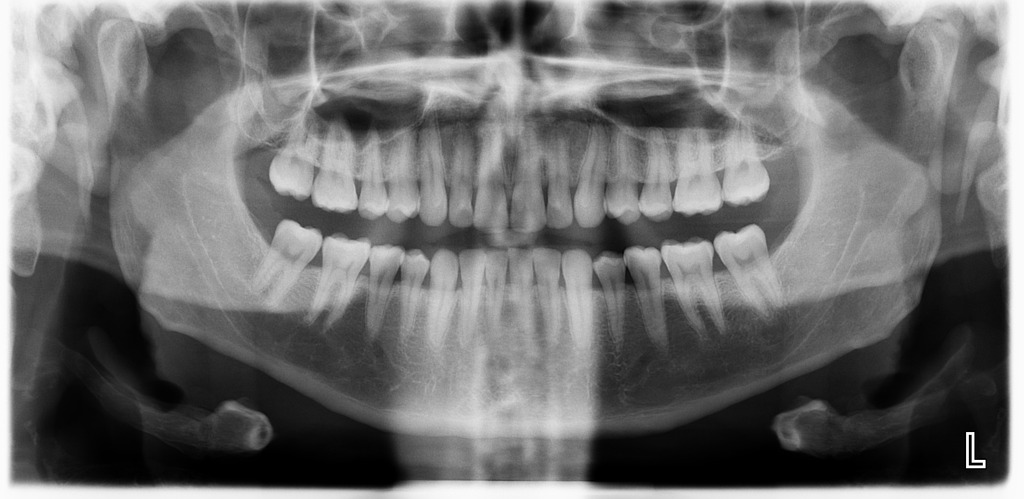

عکس دندان سالم

در این تصویر عکس دندان سالم را مشاهده می کنید